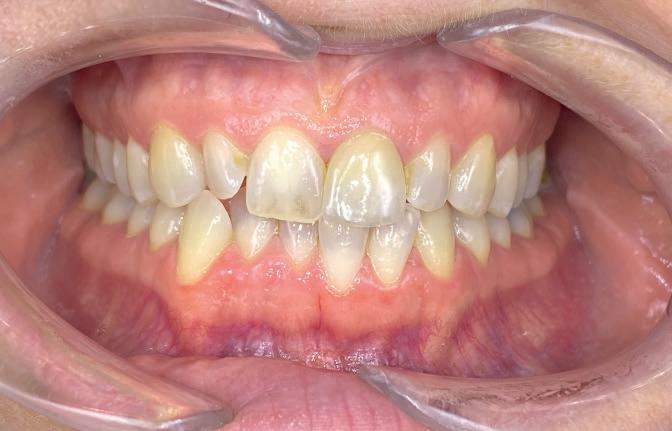

Timothy Zoltie is Head of the Medical & Dental Illustration Department, based within the School of Dentistry at the University of Leeds, in a collaborative role with Leeds Teaching Hospitals NHS Trust. He is an award-winning professional photographer and videographer, in the speciality area of medicine and dentistry. A Fellow of the Institute of Medical Illustrators, as well as a Fellow of the Royal Photographic Society, Timothy Zoltie also works as Editor in Chief of the Journal of Visual Communication in Medicine.

The School of Dentistry at the University of Leeds stands as a preeminent hub for dental education and research, distinguished by its expert faculty and state-of-the-art training facilities. Renowned as a leading centre for dental study, the school is committed to shaping the future of dentistry by nurturing the skills of the next generation of dental professionals. A unique element of the institution is that it has a dedicated Dental Photography Department, one of only a few in the world. The dental photography department at the University of Leeds has been delivering high-quality dental photography services for over 60 years, and currently photographs over 8,000 patients per year.

In reviewing the market for camera systems to use for dental and clinical photography, Timothy was looking for a compact solution that would capture the highest-quality images, while offering versatility to shoot stills and video.

solution and results

After reviewing the various options, Timothy chose the Sony Alpha a7R V Mirrorless camera system. In capturing stills and video, the camera provides the versatility Timothy was looking for in his hybrid role, where he not only photographs clinical conditions but also undertakes clinical videography. The seamless interchangeability of lenses for video and stills on a single system significantly enhances workflow efficiency. The compact form factor of Sony cameras improves manoeuvrability and user comfort, which is particularly advantageous for repetitive tasks such as intra-oral photography. Manual focusing for Timothy is crucial in dental

photography for maintaining consistent working distances and is facilitated by the Sony 90mm Macro G OSS lens. It is the only mirrorless lens in its focal range equipped with lens distance scales and ratios on the barrel.

“The Sony FE 90mm Macro G is one of the sharpest macro lenses I have used, Timothy explains. “Clarity is imperative when undertaking clinical photography and paired with a high-resolution camera such as the Sony Alpha 1 or Sony Alpha a7R V, it allows exceptional documentation of clinical detail.”

When Timothy is shooting in clinical conditions, where stopped-down apertures of f/22 are used for increased depth of field, effective lighting is crucial. Flash is the key source of illumination and the Godox MF-R76S+ Ring Flash developed jointly with Sony Europe is used with the Sony Alpha camera. This dedicated dental kit is easy to set up and delivers the required picture quality in combination. The optimised dental kit compatibility for Sony Alpha cameras provide highly accurate E-TTL functionality that produces the correct exposure on every shot, regardless of camera-tosubject distance.

Another camera feature Timothy uses is custom modes. This enables standardised settings for specific tasks, streamlining workflows and minimising errors. For example, custom mode 1 can be assigned for intraoral photography, and custom mode 2 can be designated

t imothy recommends that other dental professionals considering using sony alpha cameras should test the kits that fit their practice, explore the system’s versatility, and invest in dental photography training.

He said: “take time to understand the camera’s features and functionalities to unlock the full potential of the camera, such as how to calibrate and set up custom modes, and how to switch between them. Once calibrated, the sony system paired with the dedicated Godox MF-R76s+ for sony alpha cameras is by far one of the easiest camera set ups for dental photography and can be used by any of the dental team.”

for videography, with all the associated settings for each mode saved.

The adoption of Sony Alpha cameras at the University of Leeds has significantly elevated the quality and efficiency of dental photography and videography. Timothy Zoltie’s experience highlights the importance of a versatile and user-friendly camera system in the specialised field of dental imaging.

Timothy said: “Choosing a hybrid system has proven very advantageous, seamlessly facilitating the interchangeability of lenses for

both video and stills. This versatility enables me to effortlessly transition between filming surgical procedures and undertaking commercial healthcare photography commissions for marketing agencies or NHS institutions.

“The Sony Alpha cameras’ hybrid functionality, complemented by features such as manual focusing and custom modes, makes them ideally suited to dental photography and they have become indispensable assets for documenting clinical procedures and conditions at the School of Dentistry.” n www.masteringdentalphotography.com